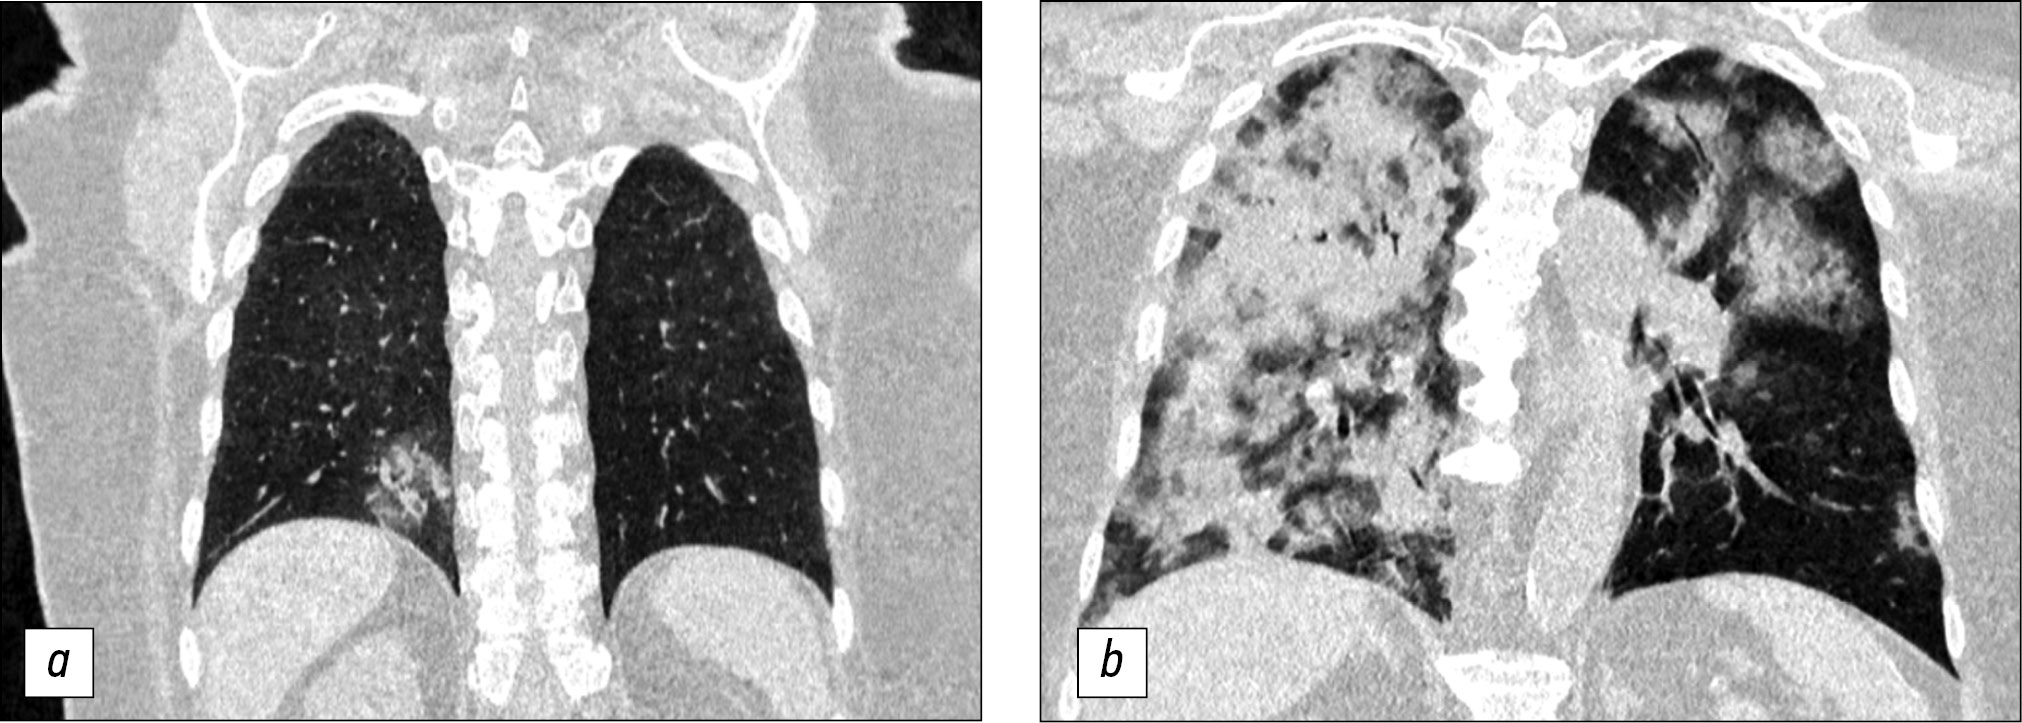

CT patterns of viral pneumonia are associated with the pathogenesis of viral infections. Most viral pneumonias have a similar pathogenesis [13]. Consequently, viral pneumonia caused by various viruses shows a similar presentation on chest CT images, which was revealed when we compared the CT images of chest organs of patients with viral pneumonias before the COVID-19 pandemic (April 2019) and during the pandemic (April 2020) (Fig. 3).

Fig. 3. Computed tomography of the chest organs; comparison of viral pneumonia images before and during the COVID-19 pandemic: a ― multiple subpleural sites of ground-glass opacity of the lung tissue (April 2019); b ― a similar presentation of an atypical pneumonia of viral origin (April 2020).

When comparing the CT detection frequency of viral pneumonia patterns in patients over the same period of time in 2019 and 2020, it was revealed that features such as the ground-glass opacity was registered in 100% of patients in both samples, crazy paving reticular changes were noted in 40% of patients in the 2020 sample and in 42% of patients in the 2019 sample, consolidation was registered in 27% and 14% of patients, and bilateral lung damage was detected in 86.4% and 71.4% of cases in the 2020 and 2019 samples, respectively.

We also showed that all the aspects of viral pneumonia detected by primary CT examination in patients with COVID-19 (mainly peripheral ground-glass opacities of the lung tissue, vasodilatation, thickening of the interlobular and intralobular interstitium, and air bronchogram symptoms) are similar to the CT aspects in acute respiratory viral infections. In this case, all of the listed radiological characteristics of viral lung damage can be attributed to damage to the alveoli and interstitium of the organ, or its edema.